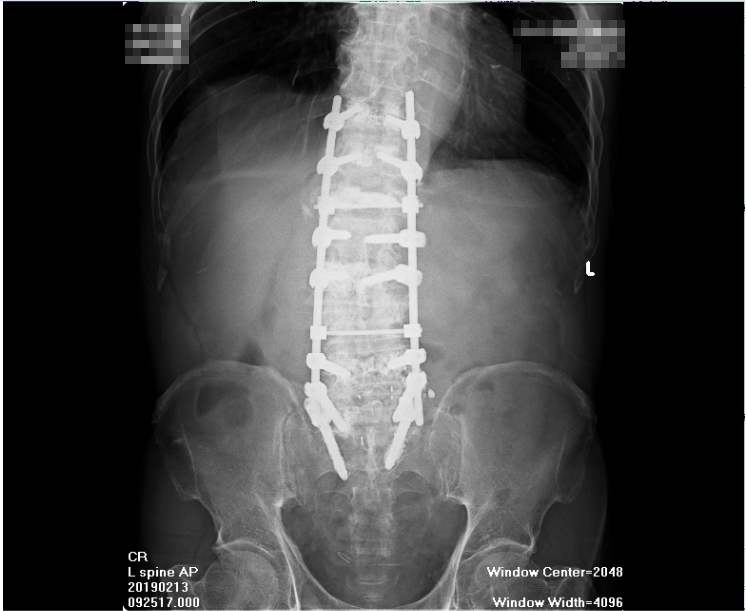

老先生家屬說他原本身體健壯,活動自如,但前兩年腰臀痛後檢查是腰椎滑脫,結果這兩年開了四次刀(包第一次括離譜的開錯部位的刀),結果,經歷四次開刀後,老先生又仍是腰腿痛麻,原本的疼痛沒有消失不說,幾次開刀後,腰上長達幾十公分刀疤,及腰椎上釘了18支鋼釘,讓老人家每天都痛不欲生,老先生家屬束手無策,卻又不知如何解決問題。

第三慘,第四次開刀完成,打了18支鋼釘,背後刀疤數十公分,鎮日疼痛,

四次大手術造成的損傷,別說這是個年近八旬的老者,就算是個壯漢,在同一個地方給他開幾次刀,上面打了這麼多鋼釘和固定板,當受傷的肌纖維形成緊縮狀態,在骨組織與鋼釘間滑動,結疤的地方這麼大,肌纖維收縮的如此嚴重,身上又有許多不屬於自己的鋼釘鋼板,光想像就令人毛骨悚然,光想像就讓人痛苦不堪,還被家人懷疑精神有問題,老先生真的只能無語問蒼天了!

就算硬組織異變在術後獲得改善,但術後軟組織形成的沾黏,肌體攣縮使活動及血循問題更加重,這也是必然,問題未解決,反而加重病況,開刀的選擇怎麼看也不對!況且,開刀所造成的傷害,是永遠無法視若無睹,常是<起手無回>,很難翻身!